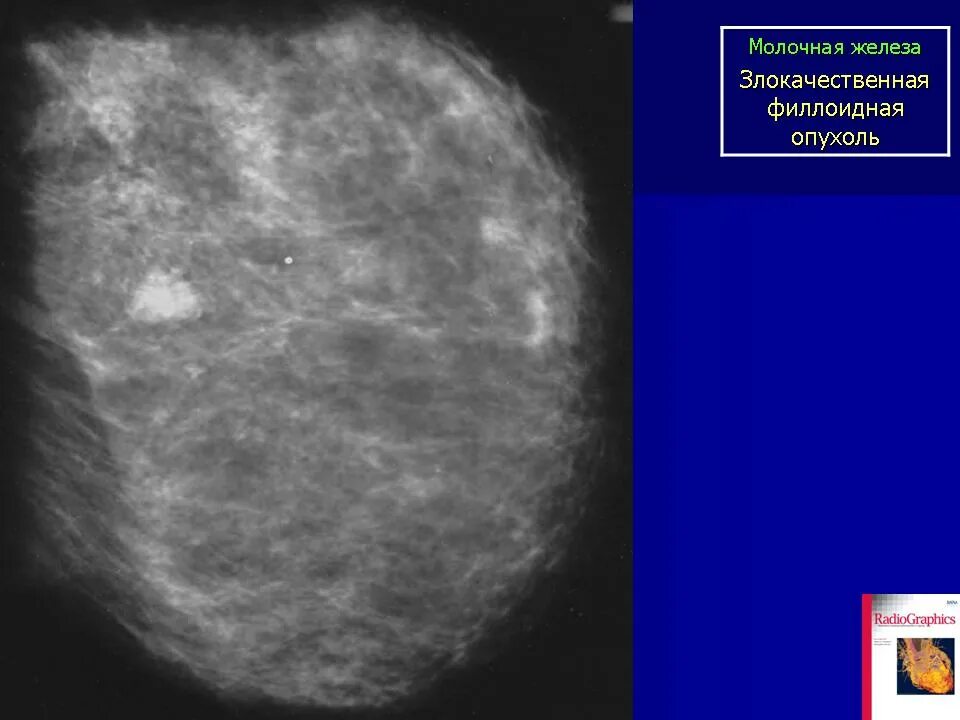

Доброкачественное новообразование молочной железы